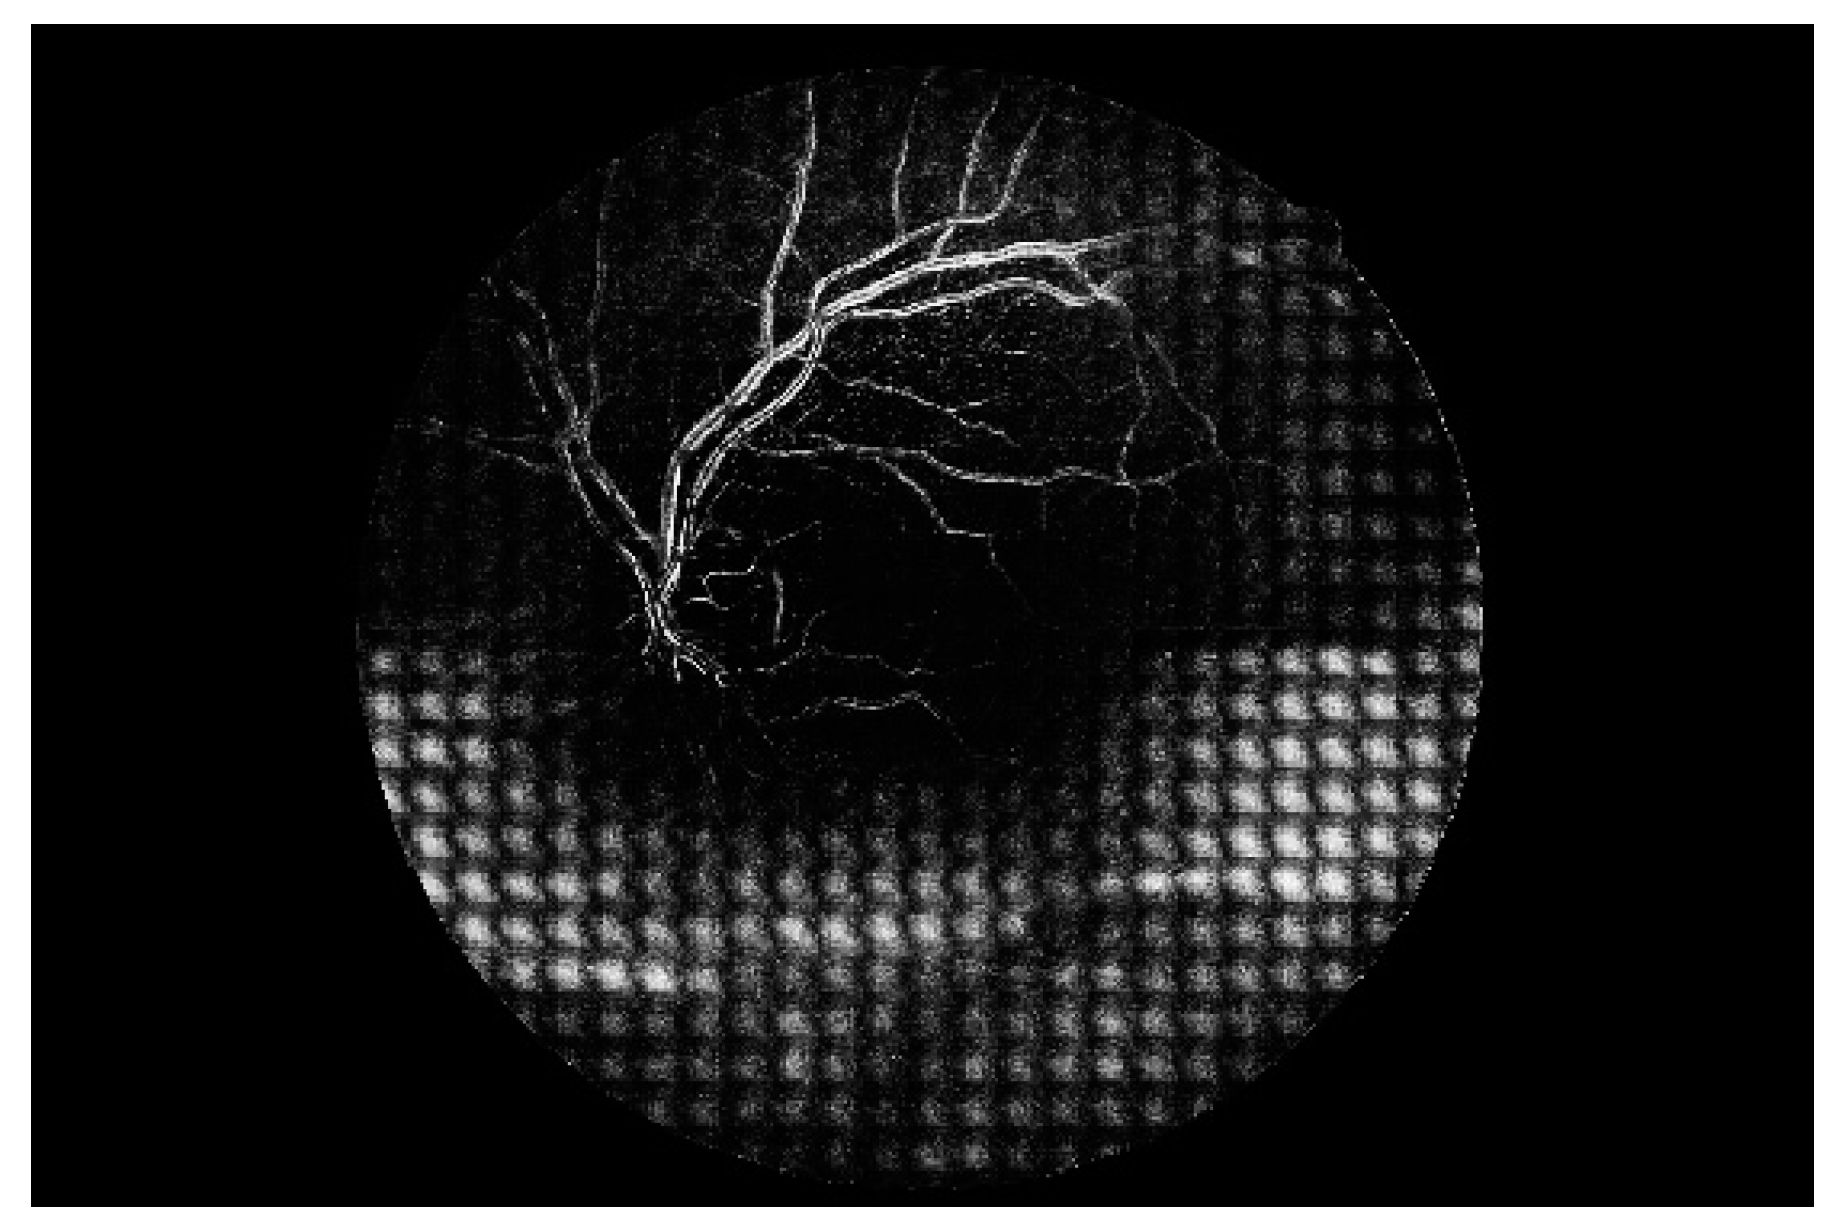

Figure 7 shows a simple example of the MLP method used in this study. The high-resolution fundus (HRF) [74] image dataset contains higher-quality retinal images compared to those of DRIVE, and provides both low- and high-quality retinal images. Figure 8 shows a low-quality retinal image. The bottom part of the image is unclear owing to white noise caused by environmental factors. Figure 9 shows a retinal vessel image created by performing vessel segmentation on Figure 8. The white noise seen in Figure 8 also affects vessel segmentation. Figure 10 is a high-quality retinal image and the white noise observed in Figure 8 has disappeared. The bottom part of the vessel stem is clearly visible, which did not appear in the original image. Figure 11 shows a retinal vessel image created by performing vessel segmentation on Figure 10. Unlike Figure 9, the bottom part of the vessel stem is shown clearly.

Figure 8. Retinal image (low quality).

Electronics 09 00767 g008

Figure 9. Retinal vessel image of Figure 8.

Electronics 09 00767 g009